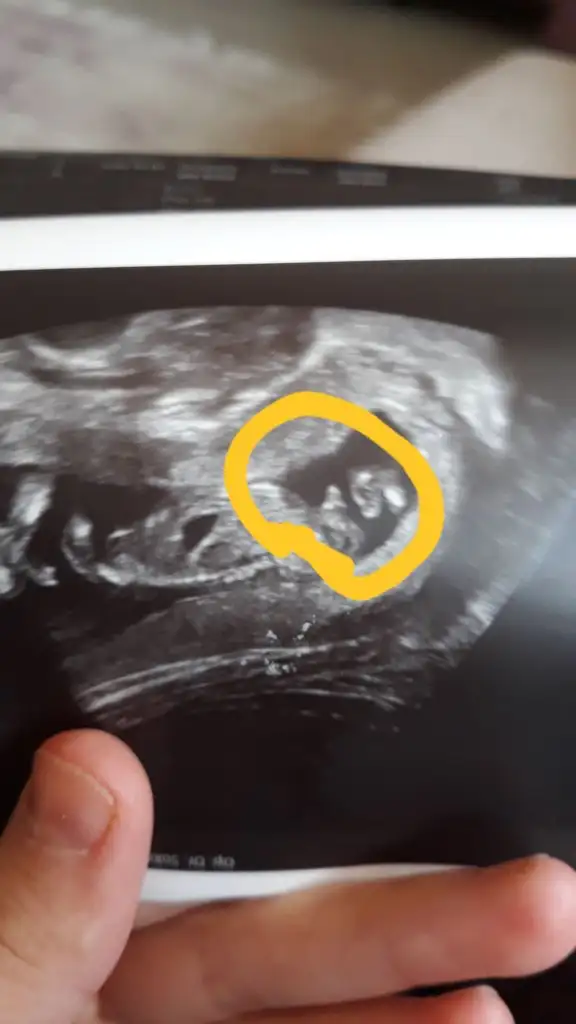

Cnm ayna gibi usg hep yüsütüydü asla kıpırdamadı neden dedim uyuyor dedi banada hiç bilgi vermez vermedi direk kız dedi kesin mi dedim kesin dedi, sinir oldum insan bir uyandırır zorlar falan 10dk bakmadı ama fotoda kız gibi yinede 20yi bekliyorum düzgün göreyim anlatsın bi doktorda ya bak fotolarıma, şu son fotoda bacak arası gözüküyor ama emin olamıyorum çünkü göstermedi doktor şurası şu diyeYüz üstü olduğunu nerden anlıyorsun canım. Ben hiçbirşey anlamıyorum ya. Doktor da demiyor şu pozisyonda becak arası şu organ var eli şu kolu şu. Son gittiğimdeki doktor söyledi sadece o da 2 dakika baktı bakmadı kalktım.

Hngisiymiş pipiKizlar beni bile tereddutte biraktirdiniz cinsiyet konusunda aksam aksam ultrasyon resmine baktimdegisirmi bilemiyorum artik ayrintiliya daha var doktor pipisi bu dedi sag tarafa bakin

Hngisiymiş pipianlamadım çizsene

Kiz kafasi obur taraftaOrası baban kafasının yanında kolları gibi geldi ama doktor dediyse doğrudur

Kiz kafasi obur taraftabu alt bolumu bacak arasiymis orasi degisirmi dedim bak simdi burda gorunen degisirmi dedi. Bilemedim artik

yav ben anlayamıyorum bende kafa popo net sadece yüzüstü böle görünce anlamıyom ozaman doğrudur